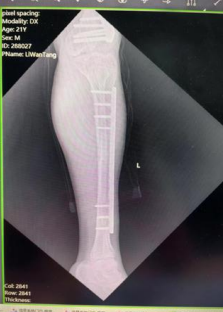

8月复诊时,患者左腿与右腿长度几乎持平

今年8月,当唐继全再次看到前来门诊复诊的李先生时,他的左腿已经与右腿长度几乎持平。随后,在唐继全的安排下,患者通过手术取出了内固定装置并进行检查。术后,李先生满心欢喜地表示,现在他终于能正常走路、跑步,日常活动不再受限了。

唐继全表示,Ilizarov外固定架可以使不愈合的骨头长在一起,使短缩的肢体延长,可以使久治不愈的骨髓炎愈合,从而让许多肢体残疾的患者恢复到受伤前的工作和生活中去。用克氏针经皮穿过骨头,外面连接一套外固定架,通过特殊装置调节外固定架就能达到矫正畸形、促进骨愈合、延长骨和肢体等作用。同时,唐继全提醒,实施Ilizarov骨延长手术后,患者需严格掌握康复程序和随访原则,避免、减少并发症的发生。